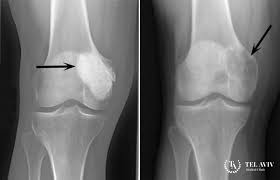

Опасность заболевания и расположение опухоли в непосредственной близости от жизненно важных структур предполагает обращение в надежное медицинское учреждение с хорошей репутацией. Лидирующие позиции среди лучших европейских клиник занимает Тель Авив Медикал Центр (Ихилов), где обследование и лечение ребенка с гигантоклеточной фибробластомой проводят опытнейшие профессионалы. Вначале врач проведет общий осмотр, ощупает опухоль для выявления степени ее болезненности и консистенции, опросит на предмет семейного анамнеза. Определить тип опухоли, подтвердить или исключить ее злокачественность помогает биопсия, с последующим изучением взятого фрагмента в лабораторных условиях. В израильской клинике ТАМС для визуализации очага поражения и окружающих тканей выполняются современные методы диагностики: рентгенография, УЗИ, КТ, МРТ.